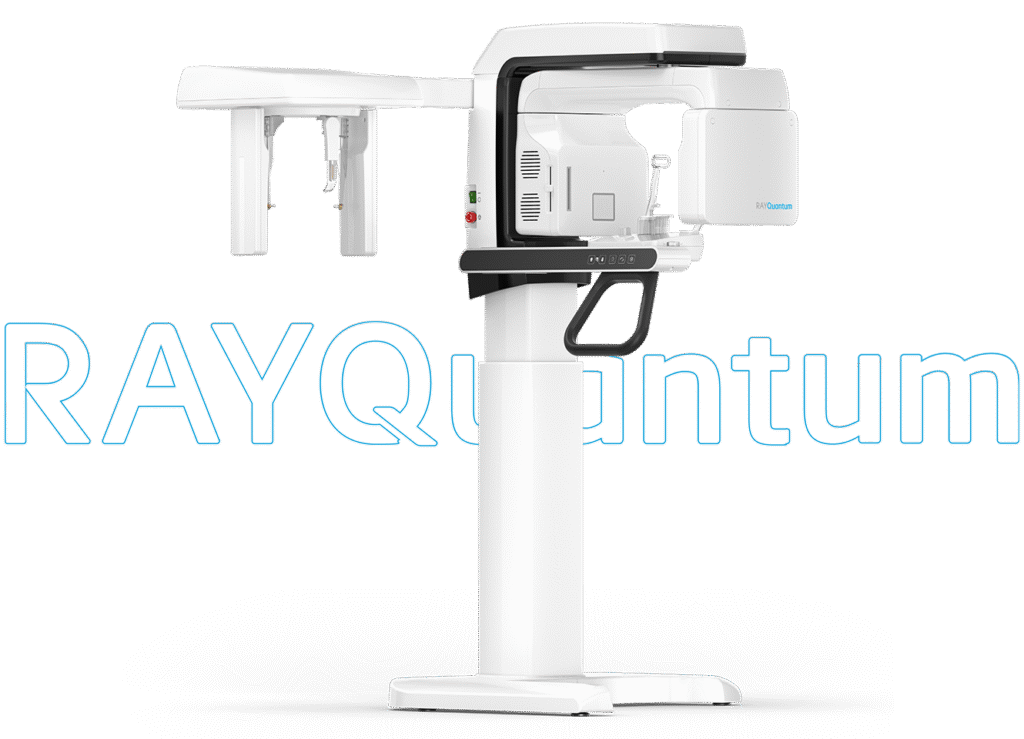

An optimized model that delivers extreme efficiency and exceptional clinical value

The expanded 16×10 FOV of RAYQuantum captures more details in a single scan, enabling precise diagnostics and comprehensive treatment planning. With high-resolution imaging and fast reconstruction times, it enhances clinical reliability and improves workflow efficiency, contributing to better patient care and treatment outcomes.

The expanded 16×10 FOV of RAYQuantum captures more details in a single scan, enabling precise diagnostics and comprehensive treatment planning. With high-resolution imaging and fast reconstruction times, it enhances clinical reliability and improves workflow efficiency, contributing to better patient care and treatment outcomes.

WHY CHOOSE RAYQUANTUM

Comprehensive support for diagnosis and treatment planning

RAYQuantum allows for quick and easy selection of the scan area through predefined FOV options, supporting a wide range of dental procedures, including implant planning, orthodontics, complex impactions, bilateral TMJ, sinus and airway analysis.